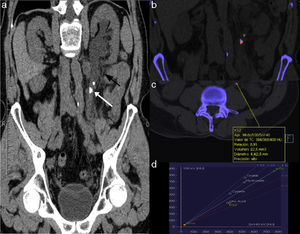

The CT modality with double energy, whether with a single source (alternating the energy or performing a double study at different energies) or with a double source (double tube) allows us to differentiate materials of similar density through the absorption variation at different energies.57,58 Most lithiases have a greater density when kilo voltage kV) is lower (80–100kV). On the contrary, uric acid calculi are attenuated in a similar way both spectra, or even more in those of greater kV (Fig. 4). This difference, quantifiable through the double energy index allows us to distinguish uric acid lithiases from the rest,59 even using low-dose protocols.60–62

Computed tomography without contrast with double energy of a patient with symptoms of left RC. (a) Curve coronal reconstruction following the ureteral tract. The white arrow shows a proximal obstructive ureteral lithiasis. The perirenal and periureteral fat shows stringiness (black arrow). (b) Coronal image of application for renal lithiasis once the double energy information is processed showing a mixed composition of the obstructive lithiasis (red=uric acid, blue=not uric acid) and a pure uric acid composition of the proximal non-obstructive ureteral lithiasis. (c) and (d) Quantification of the pure uric acid lithiasis composition showing double energy relation <1 (0.91) and a location in the graph corresponding to uric acid lithiasis (KS2). The color in this figure is visible only in the electronic version of this article.